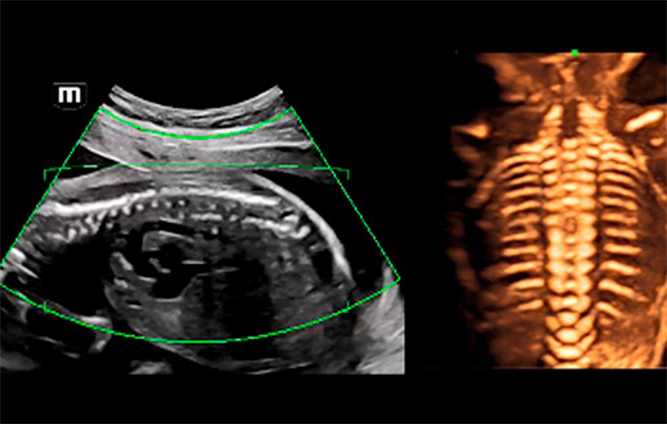

Sin embargo, la baja eficiencia del examen de ecografĆa del feto, en diversos sitios y mediciones, ha preocupado a los ecografistas durante mucho tiempo. El examen de ecografĆa 3D/4D otorga gran importancia al diagnĆ³stico ultrasĆ³nico del feto, que puede proporcionar a los mĆ©dicos la ubicaciĆ³n espacial de las estructuras con mĆ”s detalle. Sin embargo, el cambio de posiciĆ³n y movimiento del feto, el complicado ajuste de los parĆ”metros y los engorrosos pasos operativos afectan significativamente la calidad y la eficiencia. Durante mucho tiempo, hemos reflexionado sobre cĆ³mo mejorar la consistencia y la repetibilidad del examen de ecografĆa 3D para obtener un diagnĆ³stico preciso.

Para reducir la dependencia del usuario y mejorar la eficiencia del diagnĆ³stico, Mindray desarrollĆ³ una innovadora interacciĆ³n 3D/4D basada en situaciones clĆnicas para contextos tĆpicos de exĆ”menes de ecografĆa 3D (como los del cerebro, el rostro, la columna vertebral y los huesos largos del feto). Esta soluciĆ³n permite la identificaciĆ³n automĆ”tica de escenas, la optimizaciĆ³n automĆ”tica de las imĆ”genes, la captaciĆ³n automĆ”tica de planos y la cuantificaciĆ³n automĆ”tica con un solo clic. Realmente hace posible un flujo de trabajo automĆ”tico durante todo el procedimiento, lo que otorga una fuerte confianza en el diagnĆ³stico para una mejor atenciĆ³n del paciente.

ImĆ”genes de ecografĆa 3D/4D de la columna fetal